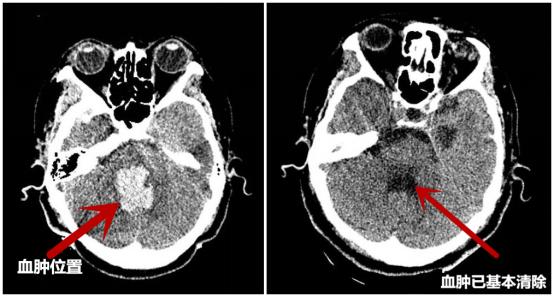

术后15天复查CT

与术前CT对比血肿已基本清除